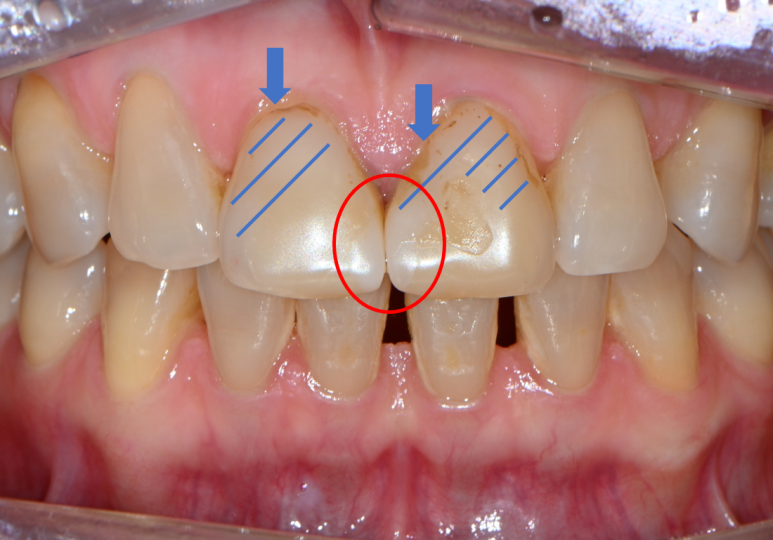

잘 보시면, 떼워놓은 앞니 레진 경계가 변색이 되서 갈색으로 보이시는 걸 확인하실 수 있죠??

파란색 빗금친 부위가 대략적으로 레진이 붙어있는 부위입니다.

빨간색으로 표시된 부위는 가운데 앞니의 빈틈을 메우기 위해 레진을 치아 옆에 붙여놓은 곳입니다.

그래도 요기는 변색은 없네요! 다만 색상의 부조화가 조금 있네요 ^^;;